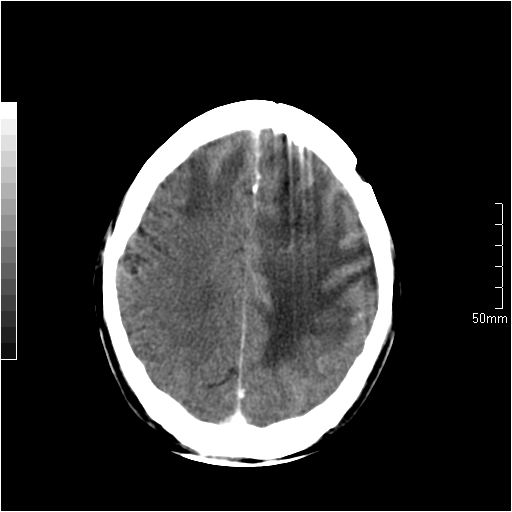

以下是引用天南地北在2007-6-25 12:39:00的发言:[br]有占位效应[br]支持术后复发

以下是引用zjzjr在2007-6-25 12:38:00的发言:[br]左侧复发,右侧转移。